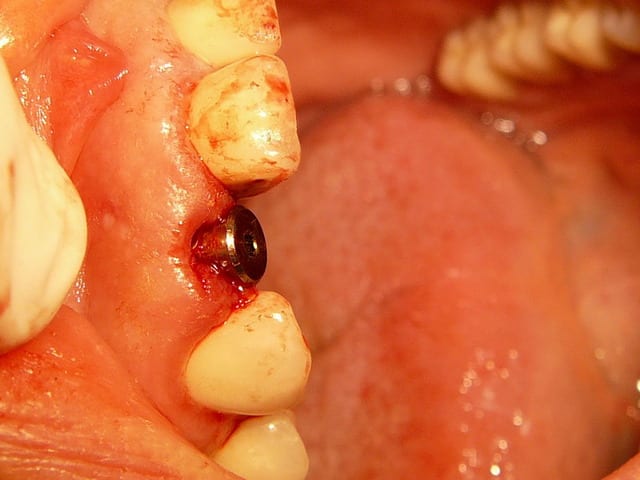

sinon, tu peux toujours partir d'un pilier standard et tu fait une provisoire dessus qui s'adapte au mieux...

comme olivier tu en sacrifies une vingtaine, mais bon, c'est pas grave tu peux t'en re-servir.